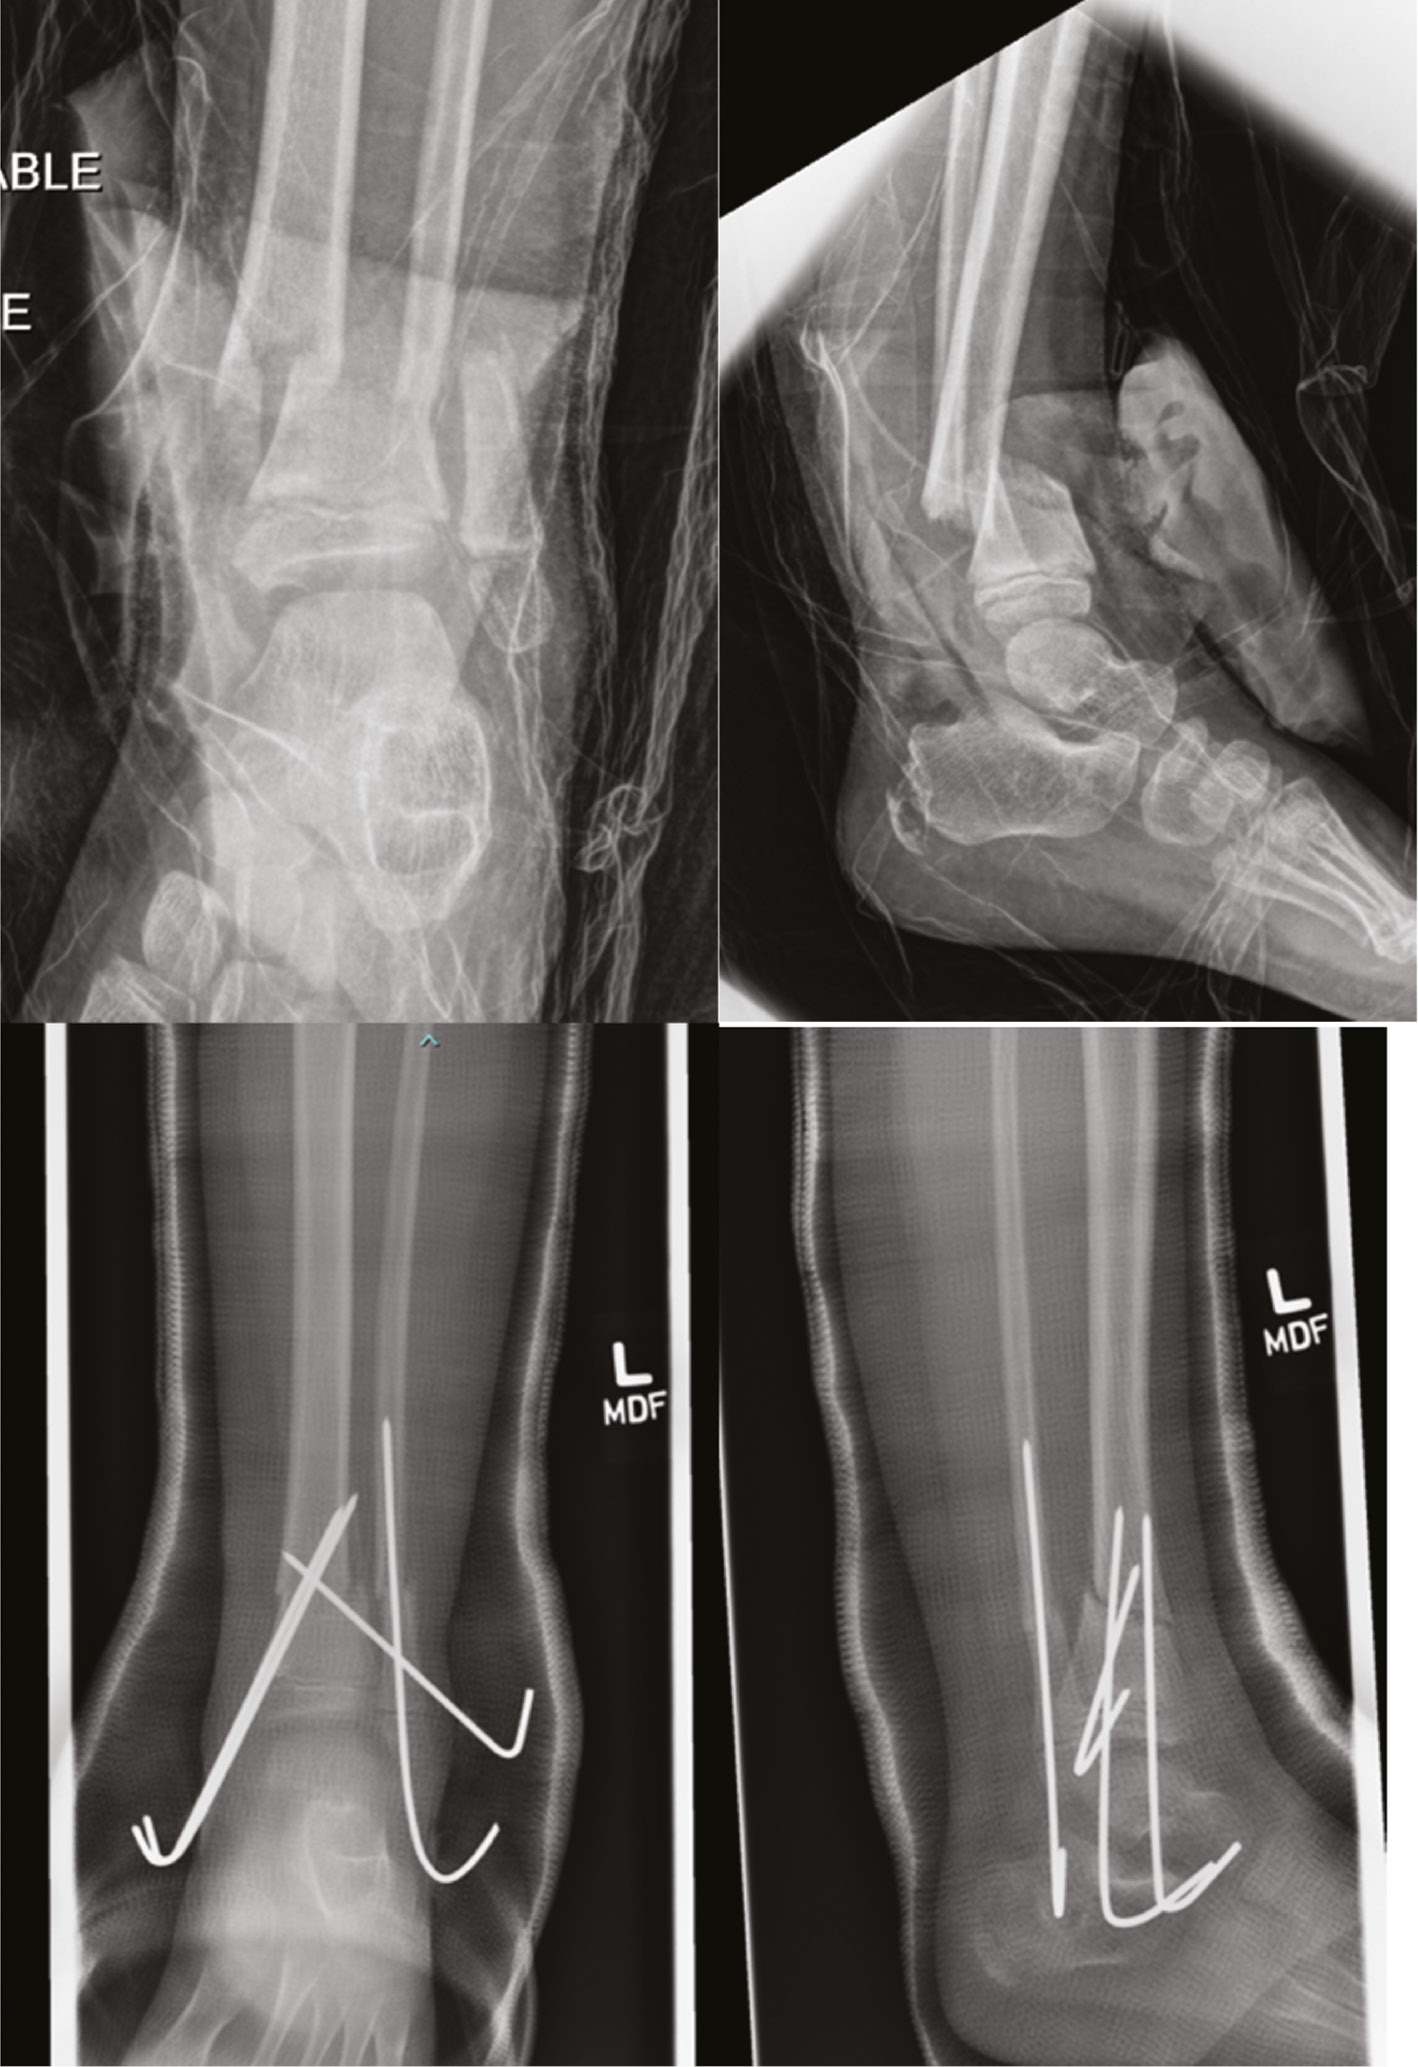

Closed reduction and percutaneous pin fixation can occur in either the supine or the prone position.60 Percutaneous fixation construct consists of two, crossed, transphyseal 3.2-4.5 mm Steinmann pins which may be placed antegrade or retrograde (Figure 15).

Figure 15. A 9-year-old football player sustained a Salter-Harris 1 distal femur fracture. Closed reduction and crossed pin fixation were performed. The pins were likely placed through the joint capsule; thus, to avoid pin tract infection that could lead to septic arthritis, they were cut off below the skin. These pins were removed in the operating room at 5 weeks after injury.